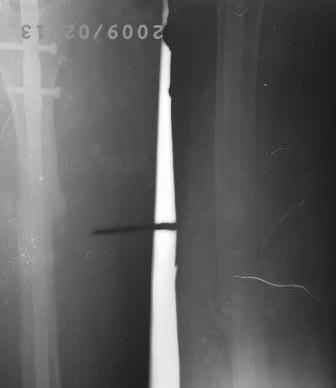

Уважаемые коллеги! Обратилась б-ная 1982г.р. 2008г. в апреле оперирована в одном солидном мед.учреждении, и/м остеосинтез штифтом лев.бедра( похоже Кюнчером), в то время была беременной, через месяц выкидыш. Со слов около 6 мес. коксит.гипсов. повязка,и до сих пор ходила с двумя костылями, кормили многими лекарствами как остеогенон. бонвива и мн. другими и даже гормонами. поправилась на 15-20кг. Но активно ногу могла поднять на 4 пальца от пола и не надолго.01.02.09.г упала на правую бок, с тех пор резкая боль в обл бедра, боиться шевелить ногой, не дает пальпировать,обратилась к леч.врачу, предлагали костно-пластическую операцию , после обратилась к нам. При тщательном исследовании выясняется что все таки имееться положительная динамика, боли уменьшается, при отвлечении можно двигать ногами, признаков рефрактуры нет, умеренная равномерная отечность, боли в мягких тканях, в надвертельной обл. боли нет, конец штифта не прошупивается. Мышцы бедра атрофированы, слабые. И на Р-гр я не вижу рефрактуру! Мой план, покой, анальгетики, УВЧ, антидепрессанты, после активация, пусть походить костылями потом без оних, реабилитация. После польной восстановлении решить вопрос удалении штифта. В отд. идет дискуссия по поводу рефрактуры, и о удалении штифта. Уважаемые коллеги помогите советом! С уважением Абдурашид.

Чтобы судить о рефрактуре хотелось бы увидить снимки лутшего качества и если имеютса до повторной травмы, но и по этим видно что есть угловое смещение. Я бы советовал разсматреть вариант удаления стержня с заменой на интрамедулярный блокирующий по статическому типу с последующей ранней дозированной физ. нагруской, ЛФК.

Даже на такой "микро" рентгенограмме видна угловая деформация. В чем проблема сделать снимок бедра на всем протяжении? Боль, скорее всего,

Да, на Р-грамме имеется угловая деформация бедра и искривление штифта, но клинически оно мало заметно,в обл. деформации подвижность

не определяется, укорочение 1,0-1,5 см, б-ная очень нервозная, капризная (обычно таким б-ным что-то "умное" делать боишься -авось!), и ряд других факторов , подумал может, все обойдется более экономным методом.

Оставить на потом нельзя, попробую закрытую остеоклазию с коррекцией деформации и искривлении штифта (оказалось штифт Еланского для голени- где нашли и почему?), удалении из надвертельной обл,

рассверливание и реостеосинтез блокируюшим гвоздем статически, может,